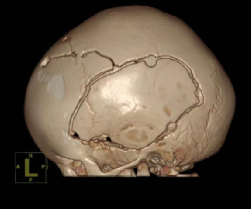

9月,凯凯被送入手术室。在先进的神经导航系统和术中监护技术的辅助下,手术团队开始了精细操作。医生们精准地铣开双侧已骨性融合的颞鳞缝,小心游离骨瓣并进行减张固定,同时松解了紧张的冠状缝。整个手术过程犹如一次精密的“颅骨雕塑”,在微创理念指导下,操作精准无误,未对脑组织造成任何损伤,成功实现了颅腔容积的有效扩大。

术后

术后,凯凯的恢复情况令人欣喜。最直观的变化是他的情绪状态——此前那个稍有不顺就哭闹不安、易激惹的小家伙,变得平静、安稳了许多,笑容也更多地回到了他的脸上。这一转变,印证了手术成功解除了颅内高压,缓解了因脑组织受压所致的不适感。